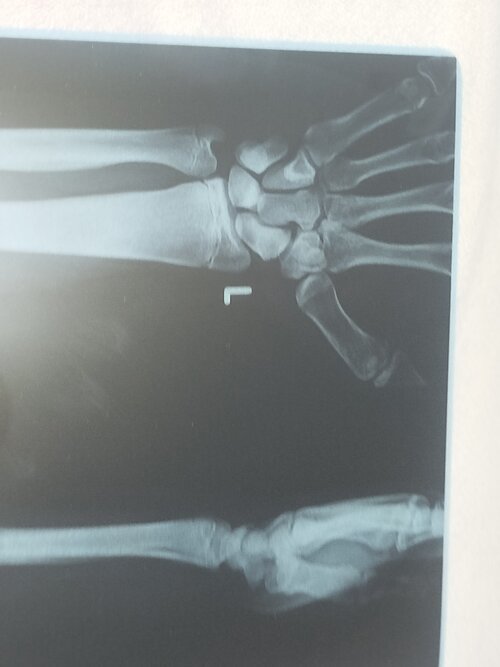

I wouldn't rn since ur 16 but get an xray if u can to see if ur plates are even close to closing (also pls rep 😢)

i did look + wym by rep?

look

Attachments

• 1000291322.jpg

1000291322.jpg

2 MB · Views: 0

U got like a 1-3 years left of growth (late puberty) the AI won't do much